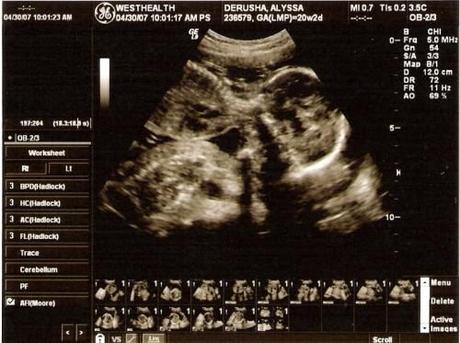

Foto | Jason DeRusha